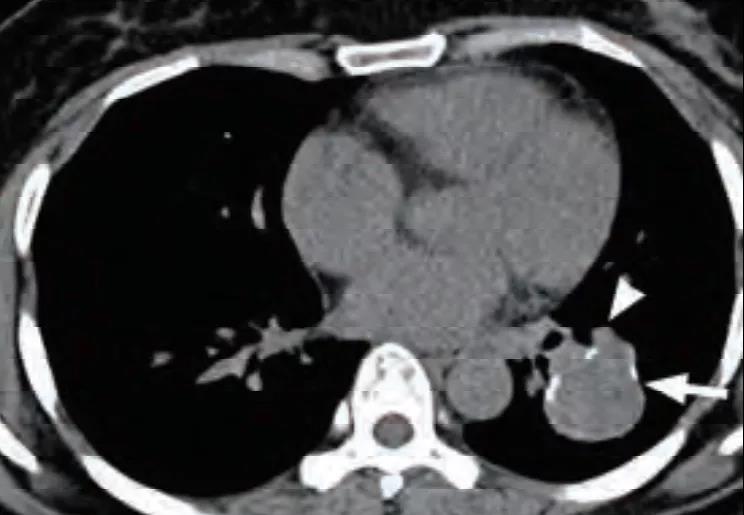

可伴特征性尾征(图 3),即占位边缘的尾状突起,多位于近端靠近肺门一侧